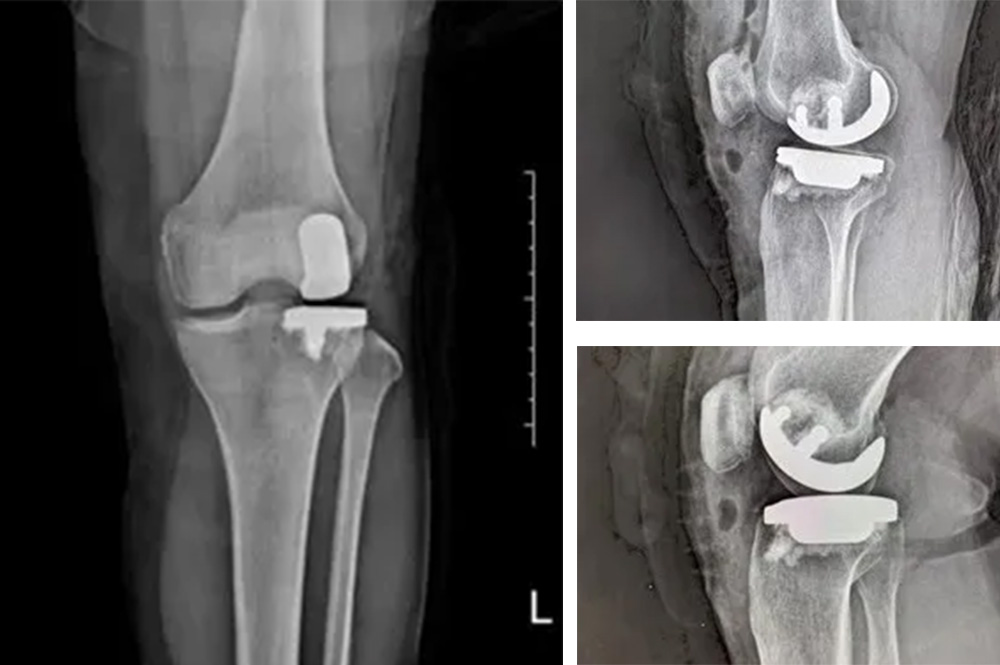

我院骨科主任罗医生介绍,膝关节分为内侧、外侧和髌股三个间室。鲍奶奶的问题主要集中在膝关节外侧间室,而内侧和髌股关节相对完好。

“传统全膝关节置换会切除所有关节面,而单髁置换只替换病变的部分,保留了健康的韧带和软骨,更符合‘精准医疗’理念。”罗医生说。

经过详细的体格检查、影像学评估和三维重建,医疗团队确认鲍奶奶的情况非常适合进行膝外侧单髁置换术。这种微创手术创伤小、恢复快,能够最大程度保留膝关节的自然结构和功能。

手术使用了最新的单髁假体系统,这种假体设计更符合人体工程学,能够更好地恢复膝关节的自然运动轨迹。

膝外侧单髁置换术是膝关节置换领域的重要进展。与全膝关节置换相比,它具有明显优势:手术创伤小,仅置换病变部分;保留更多自然结构和韧带;术后恢复快,住院时间短;术后膝关节感觉更自然,活动度更好。